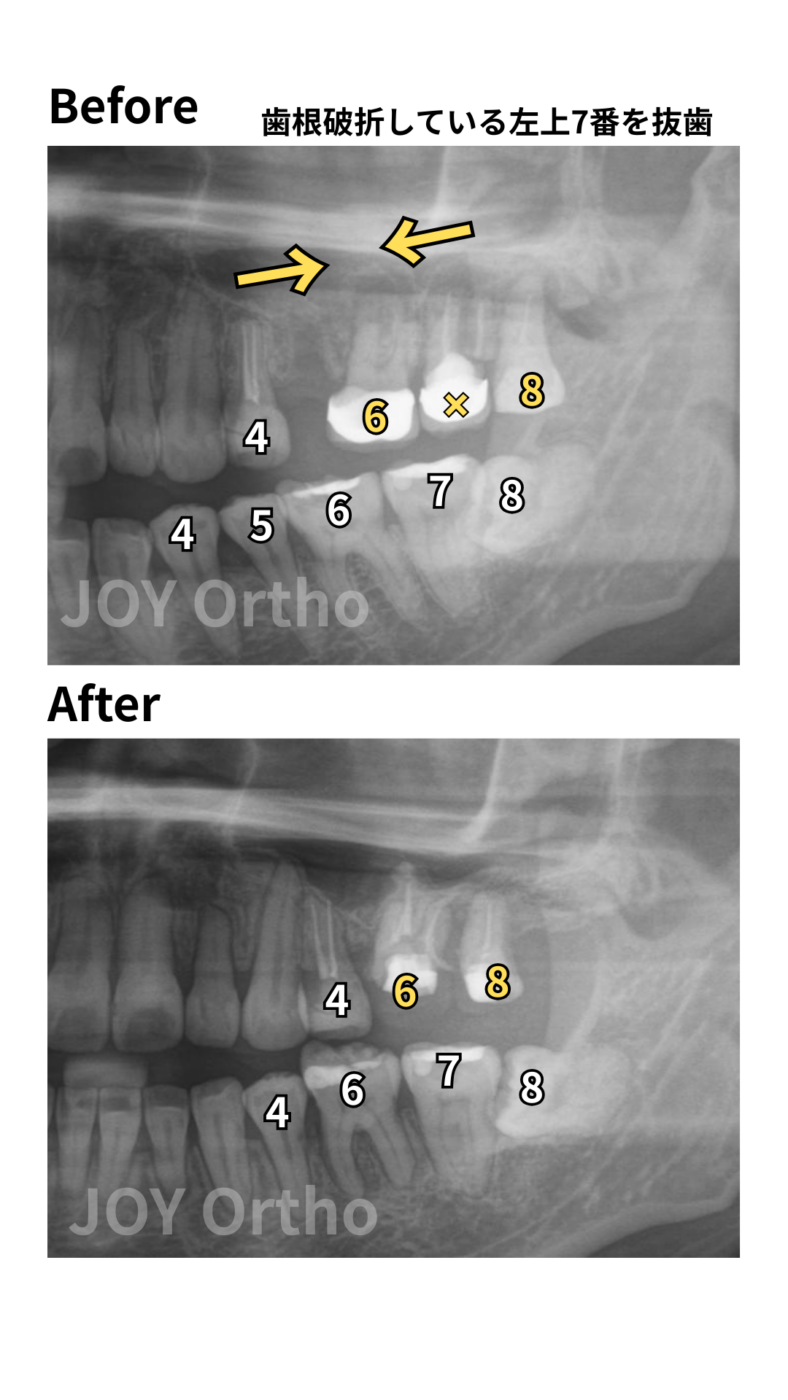

◆【症例10】パターン④ 上顎7番が歯根破折のため抜歯、8番を利用してインプラントを回避したケース

症例の概要

左上7番が歯根破折しているため、抜歯が必要になりました。左上7番を抜いた場所に左上8番を動かして7番の代わりに使用した症例です。

また、著しい上顎前突だったため、通常なら4番を抜歯したい症例ですが、すでに5番が抜歯されていました。結果的に左上は2本分のスペースを閉じることになった難症例です。

症例10

①主訴:出っ歯、左上7番の根が折れている。左上のインプラントを避けたい。

②診断名:上顎前突症、叢生

③初診時年齢:39歳

④治療に用いた主な装置:マルチブラケット装置、

歯科矯正用アンカースクリュー

⑤抜歯部位:右上4番、左上7番、右下8番、左下5番

⑥動的治療期間・通院回数:3年3ヵ月・約36回

⑦治療費概算:約105万円(税込、検査・診断料+矯正治療費+大臼歯加算+スクリュー費)+毎回の処置料3,300~5,500円(税込)

⑧リスクと副作用: 歯根吸収の可能性がある。大臼歯移動のため、通常より治療期間が延長する可能性が高い。